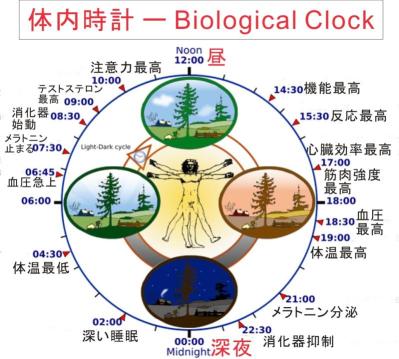

眠くなるのは脳神経の一部がホルモン(メラトニン)を分泌し、血液で体中に巡回し「休憩時間」だと告げる--下画像参照